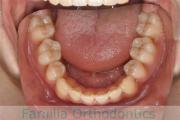

上の前歯の並びが気になるのできれいにしたい、ということで来院されました。マウスピース型矯正装置のひとつ、インビザライン/InvisalignR(薬機法および医薬品副作用被害救済制度の対象外)を用いて治療しました。

非抜歯で2年弱、20回程度の通院で治療が完了しました。

マウスピース矯正は、患者さんの協力に治療結果が左右されるところはリスクと言えるかもしれません。

- ≫治療後

-

※注意※ インビザライン Invisalign®は、国外のアライン社工場で製造されたマウスピースを輸入する形式となるため、国内では未承認器材扱いです。このため、薬機法対象外の矯正歯科装置であり、医薬品副作用被害救済制度の対象外となる場合があります。ただしすでに我が国を含む海外の多数の国で矯正治療に用いられております。当院では、症例を選んで選択させていただいておりますので、インビザライン使用のご希望に添えない場合もございます。

上顎

下顎

前歯の関係など